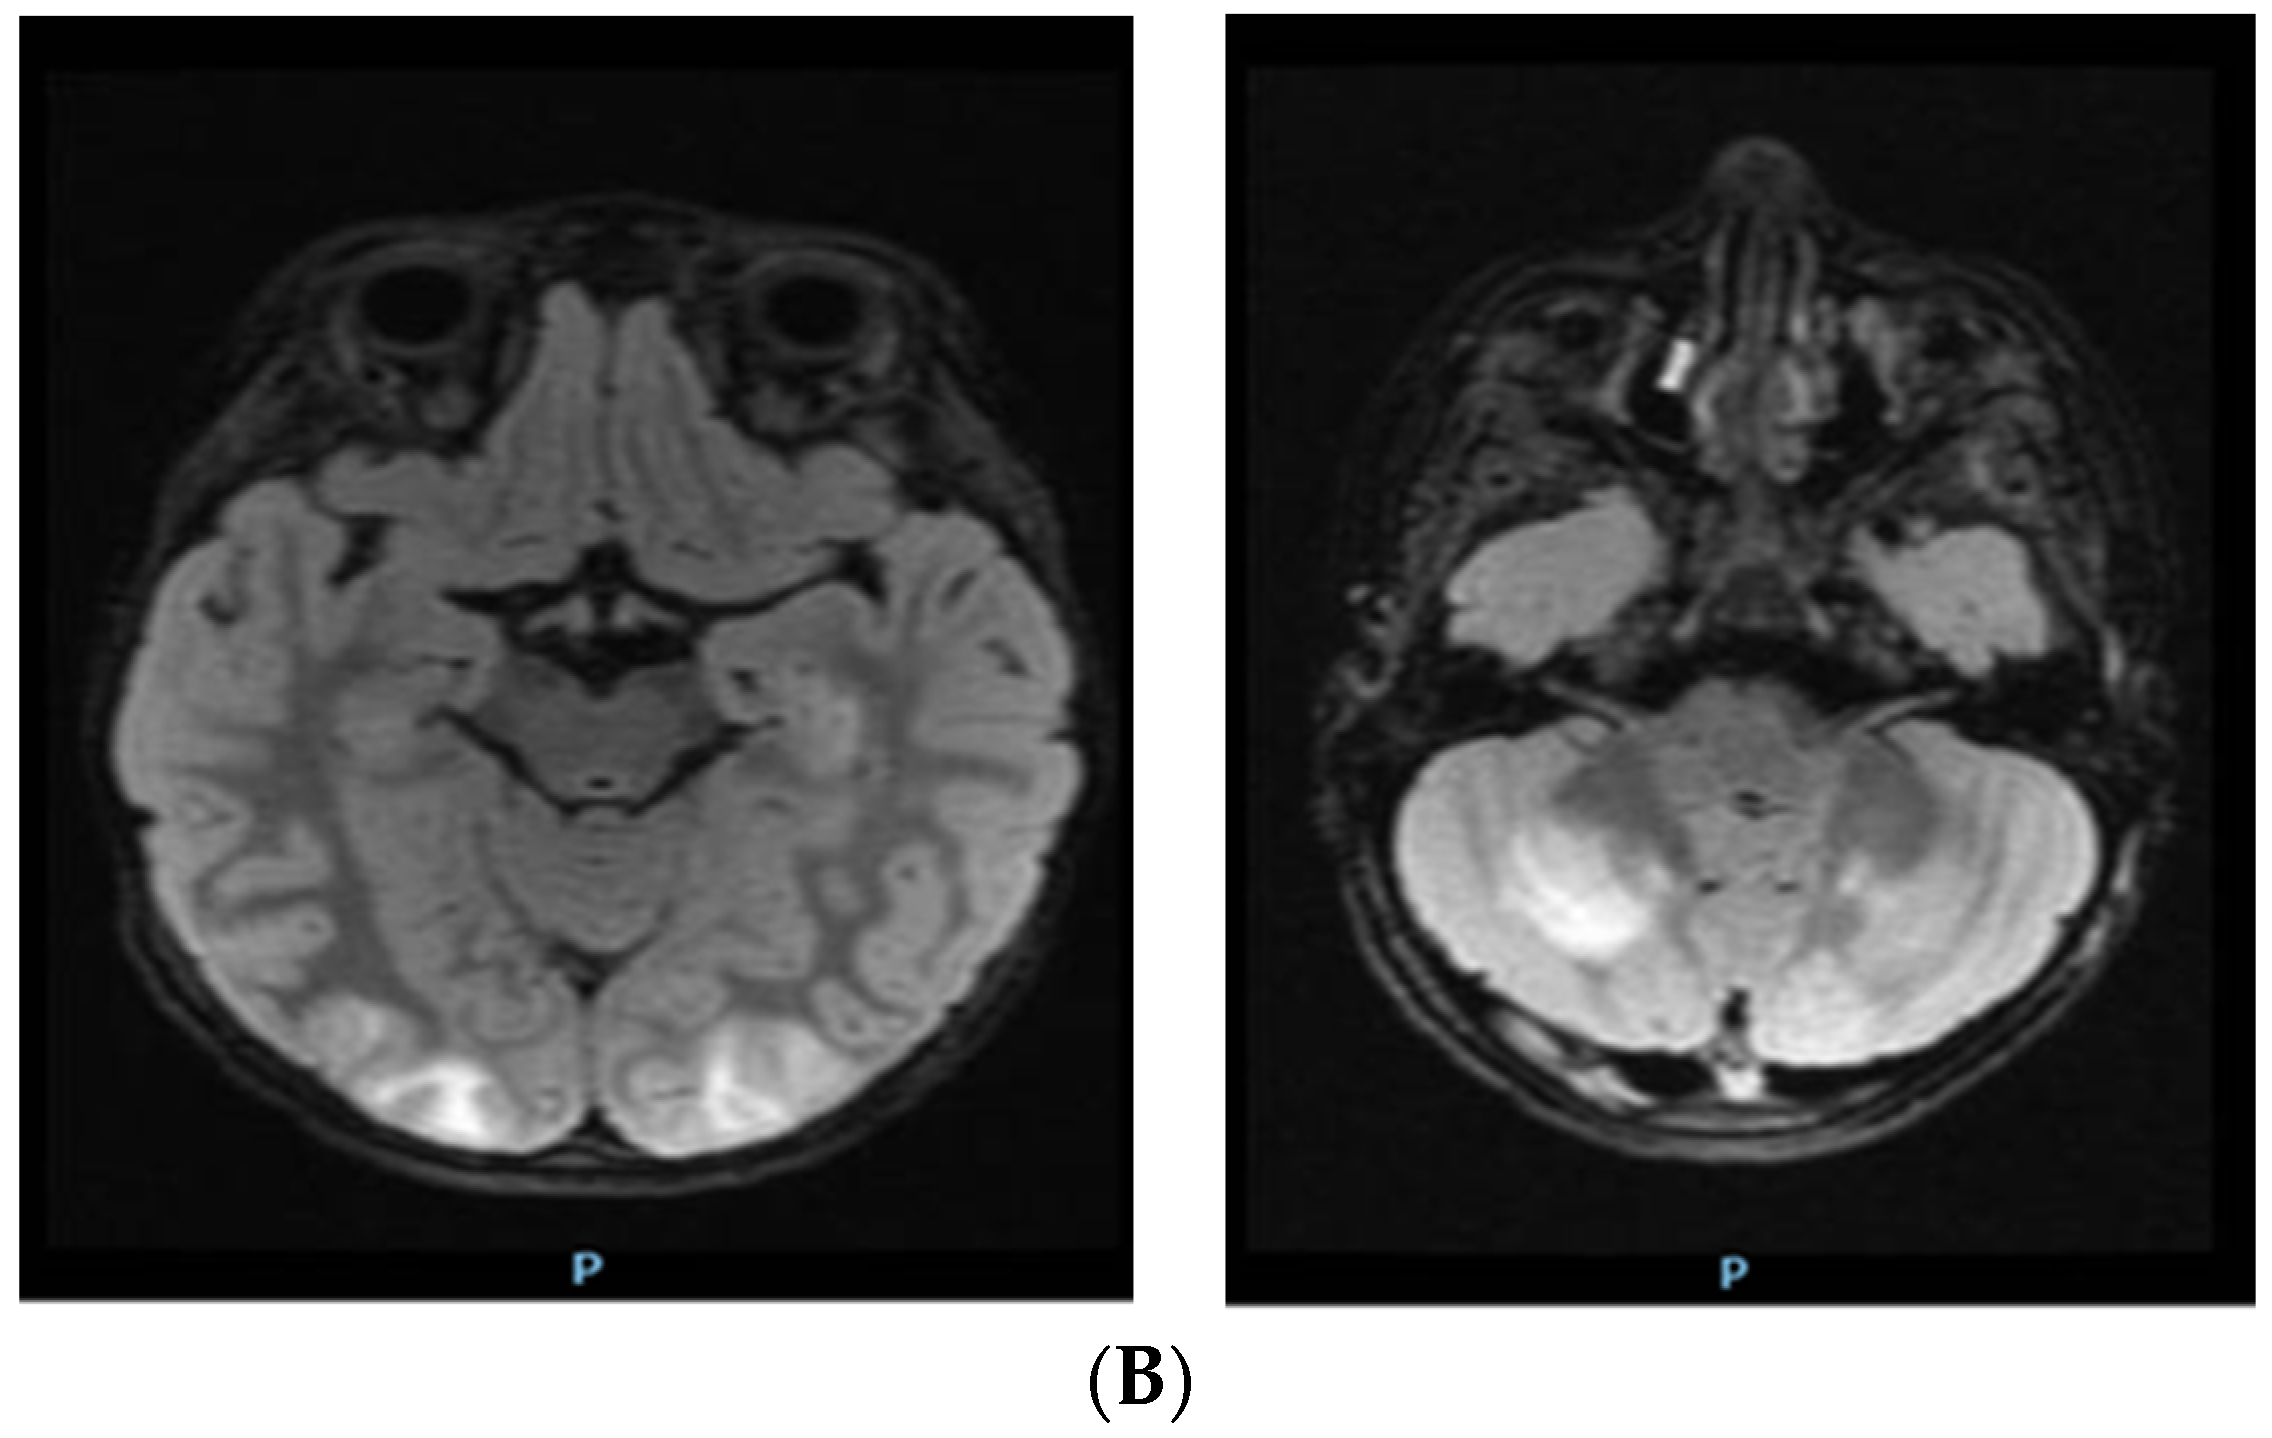

2. Case Report